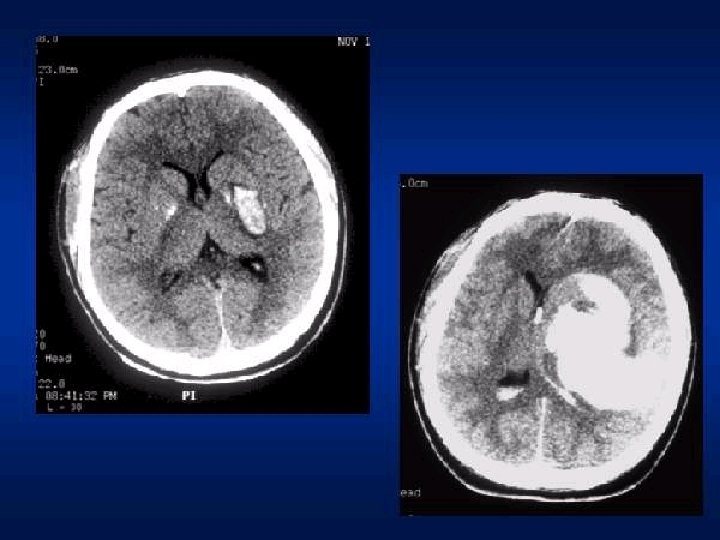

CLASSIFICAÇÃO Hematomas epidurais ◦ Osso e dura-máter ◦ Lente biconvexa, temporal ou têmporo-parietal, ◦ Ruptura da artéria meníngea média, causada por uma fratura. ◦ Tto precoce melhor prognóstico. ◦ Sintomático, > 1 cm, fossa posterior ◦ Clínica: intervalo lúcido seguido de “fala e morre”.

Hematomas Epidurais Ou extradurais ocorrem mais comumente por fratura da porção escamosa do osso temporal, em cuja face interna corre (em um sulco) a artéria meníngea média. Uma lesão desta causa um hematoma entre o osso e a dura-máter, de formação rápida, porque a pressão no vaso é arterial. Como a dura é aderida ao osso, os hematomas epidurais são circunscritos e arredondados. Forçam o lobo temporal em direção medial e provocam hérnia de uncus.

CLASSIFICAÇÃO Hematoma ◦ ◦ ◦ ◦ subdural: Mais freqüente que hematoma epidural Veia entre o córtex cerebral e o seio venoso. Recobrem toda a superfície do hemisfério. Comprometimento cerebral mais grave Prognóstico mais reservado que epidural Tto precoce, se sintomático Atraso maior que 4 hs: Mortalidade 59 69%;

Hematoma subdural A velocidade de formação do hematoma é variável de horas a dias. Inicialmente o sangue se coagula, mas vai lentamente se fluidificando por ação de fibrinolisinas. Os hematomas subdurais agudos podem causar hipertensão intracraniana elevada e hérnias. Além do tipo agudo, os hematomas subdurais podem ser crônicos, isto é, desenvolver-se lentamente, ao longo de semanas, após traumas pequenos esquecidos pelo paciente e desconhecidos familiares. São comuns em idosos e podem ser bilaterais

Hematoma subdural O quadro clínico é de deterioração gradual das funções mentais e da consciência, chegando ao coma, devido à compressão cerebral. Hematomas subdurais também podem ocorrer na infância por trauma obstétrico ou quedas.

FISIOPATOLOGIA DOS TCE * Hematomas Subdurais Agudos

Hematoma subdural